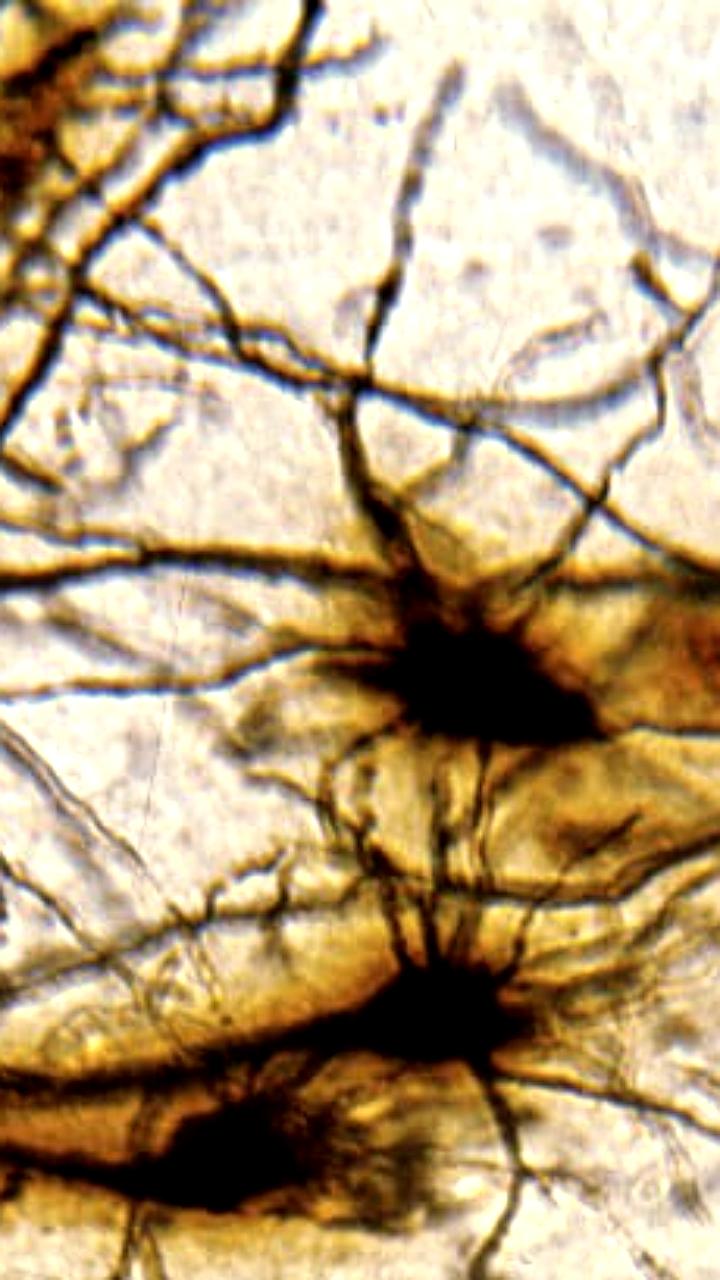

Ученые из Пенсильвании обнаружили нейроны, способные блокировать хроническую боль